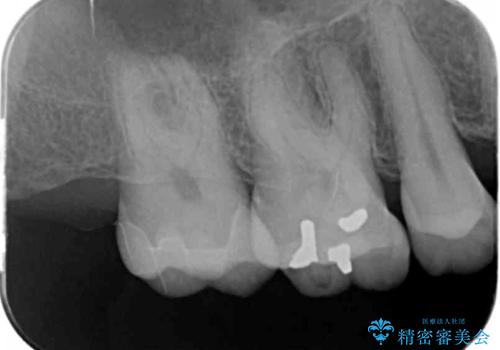

- 昔、治療された銀歯が気にな流ということを主訴で来院された患者様です。

銀歯を外し、虫歯治療を行い、セラミックインレーにて治療しました。

銀歯を除去し、虫歯をとって、セラミックインレーにて治療を行いました。